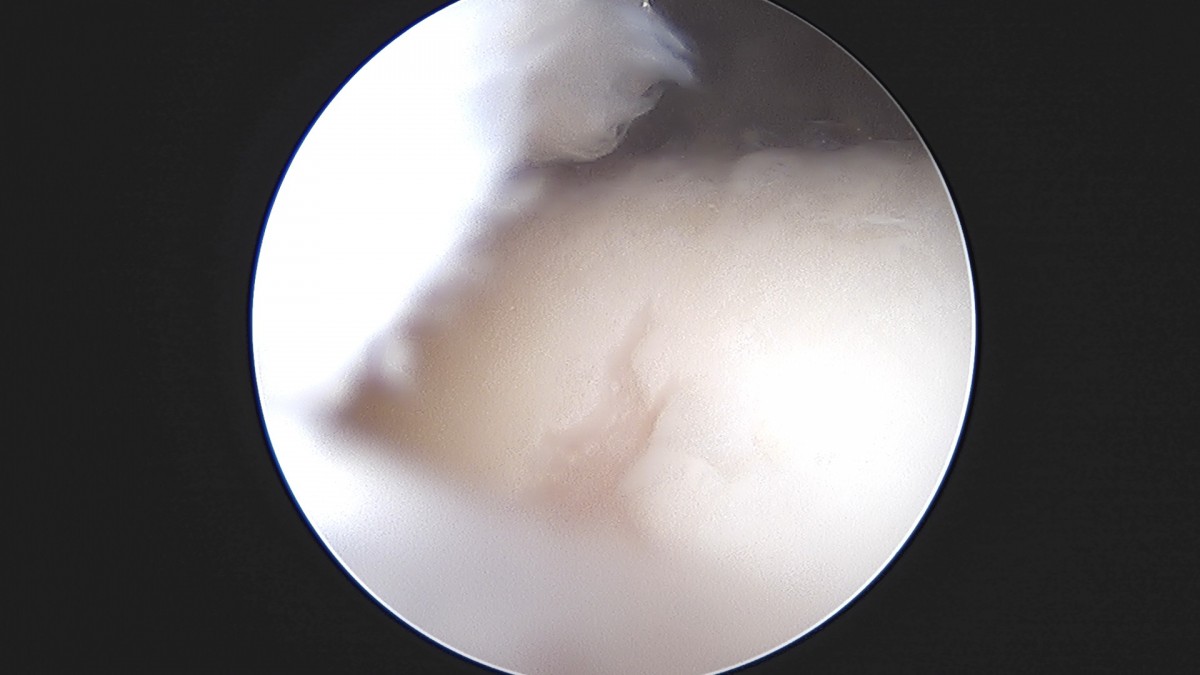

이재상원장님 무릎 반월상 연골판 절제술 최용O 환자

작성자 최고관리자 댓글 0건 조회 379회 작성일 25-09-16 15:57